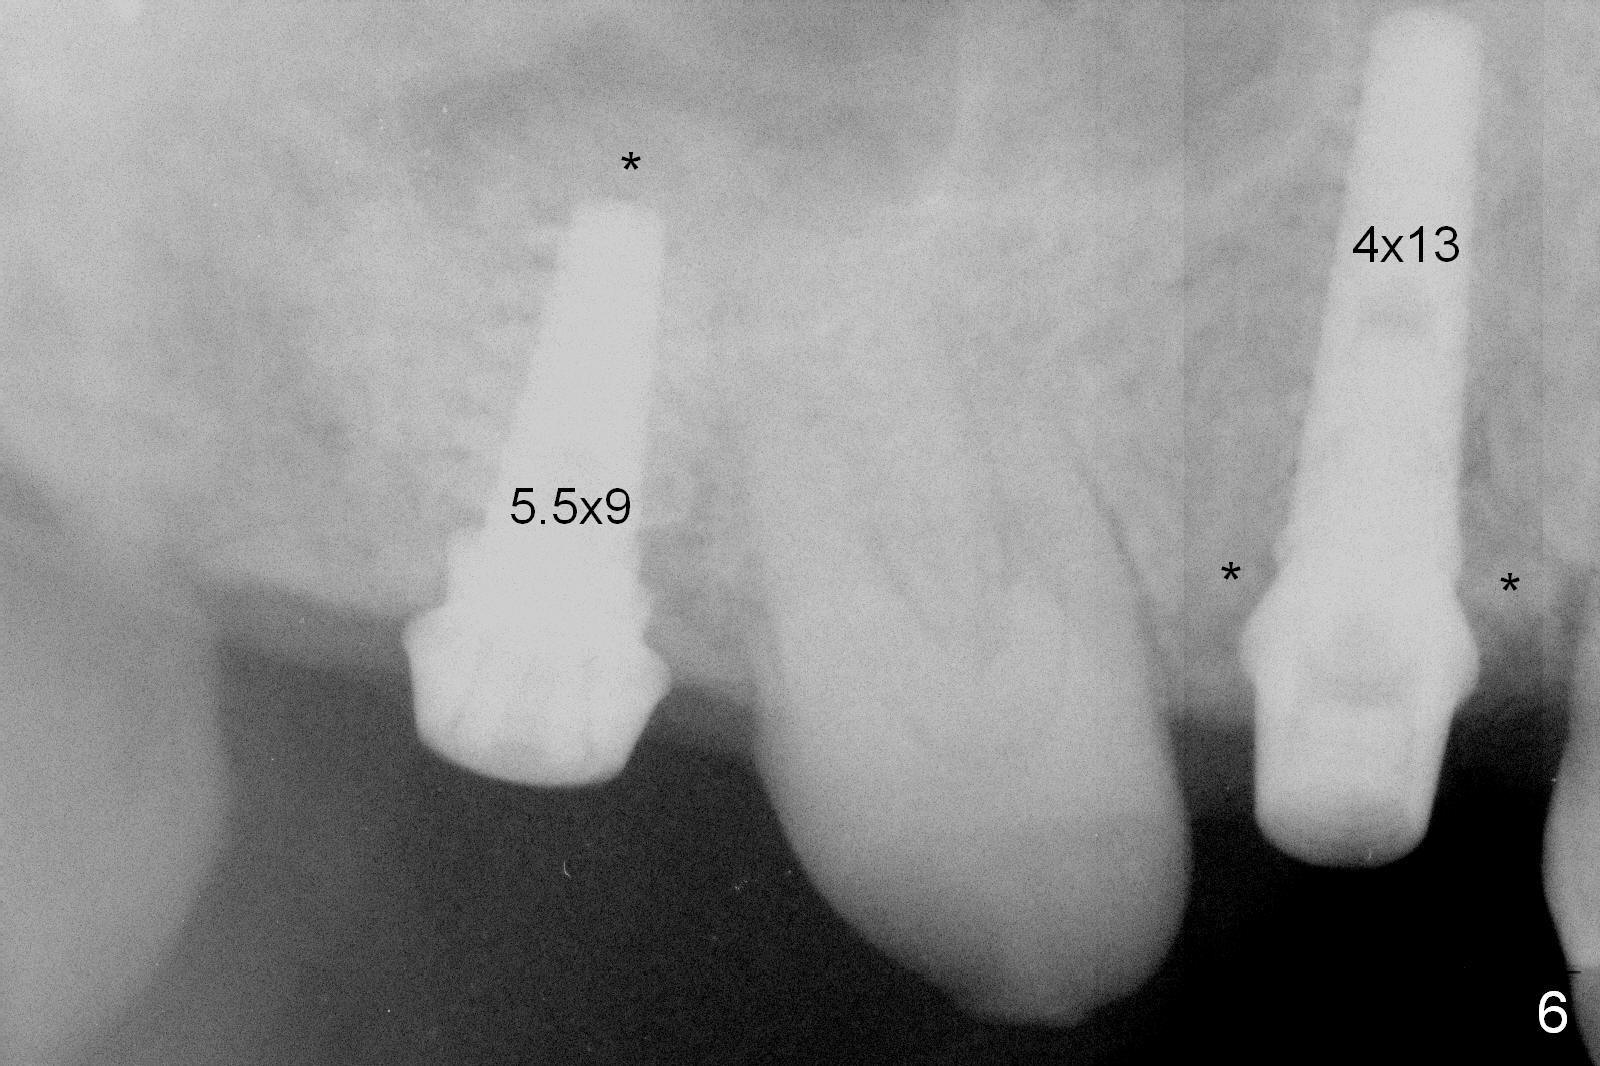

Preop exam shows posterior occlusal collapse (Fig.1) with #3 lost crown and #4 residual root. There is no ridge atrophy at #2 buccopalatally (Fig.2). The root stump of the tooth #4 is oblong, apparently consisting of 2 roots (Fig.3). There is a pointed septum at #4 socket (Fig.4, severe palatal wear of the anterior teeth (^)). After the septum is flattened with surgical handpiece and #8 round bur, 1.6 mm drill is used to start osteotomy in the septum, followed by Magic Drills (MD) and Magic Expanders (ME) alternatively. Osteotomy at #2 is initiated with Magic split, followed by MD and ME in the same manner. Dummy implants are tried in (Fig.5). Because of limited vertical height, Magicore (5.5x9(1) mm) is placed at #2, while a 4x13 mm FC implant 1-2 mm deeper than usual at #4 (Fig.6, ~ 55 Ncm). When a 5x4(2) mm pair abutment is placed at #4, there is no clearance between the Magicore at #2 and the abutment and the opposing dentition. A splinted provisional is fabricated at #3 and 4 to increase the posterior vertical height (Fig.7 P,8). In fact the occlusal contact is confined to the portion of the provisional at #3. The provisional has to extend to #4 to keep bone graft (Fig.6 *) and collagen plug in place. Liquid food is recommended at least 2-3 weeks, since there is no functional occlusal contact on the left. When the wound heals at #4 approximately 2-3 weeks, the splinted provisional can be sectioned with removal the portion at #4 to reduce micro-movement. By the evening the patient is doing well without nasal hemorrhage (sinus lift at #2 (Fig.6 *) or TMJ disturbance (due to increased vertical height).